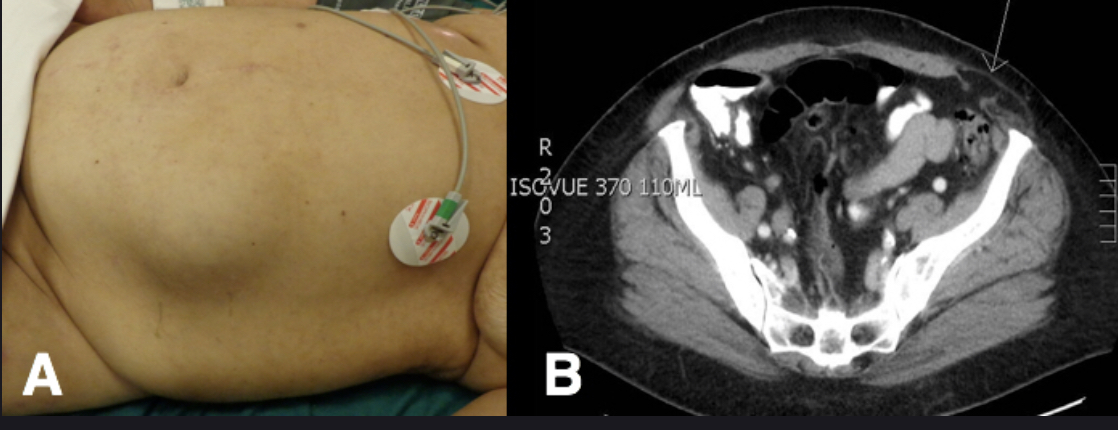

Post op: (see image)